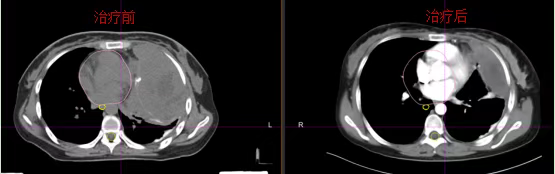

Treatment Outcomes:

Pre-treatment: The massive tumor caused significant compression, displacing the heart and esophagus to the right.

Post-treatment: Marked tumor regression was achieved with complete decompression, allowing restoration of normal cardiac and esophageal positioning. The patient's symptoms of chest tightness and dyspnea significantly improved.